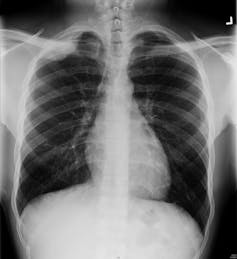

An x-ray image shows shades of grey, which is just how much of the x-ray beam manages to get through your body. If the part is very dense (like bone) it will come up white, if it is less dense (like your lungs) it will come up as a darker shade of grey.

Radiographers (the people who work the x-ray machines) can control the amount and strength of the x-ray beam (just like you can make light dimmer or brighter) so that the body parts they want to see come up on the images.